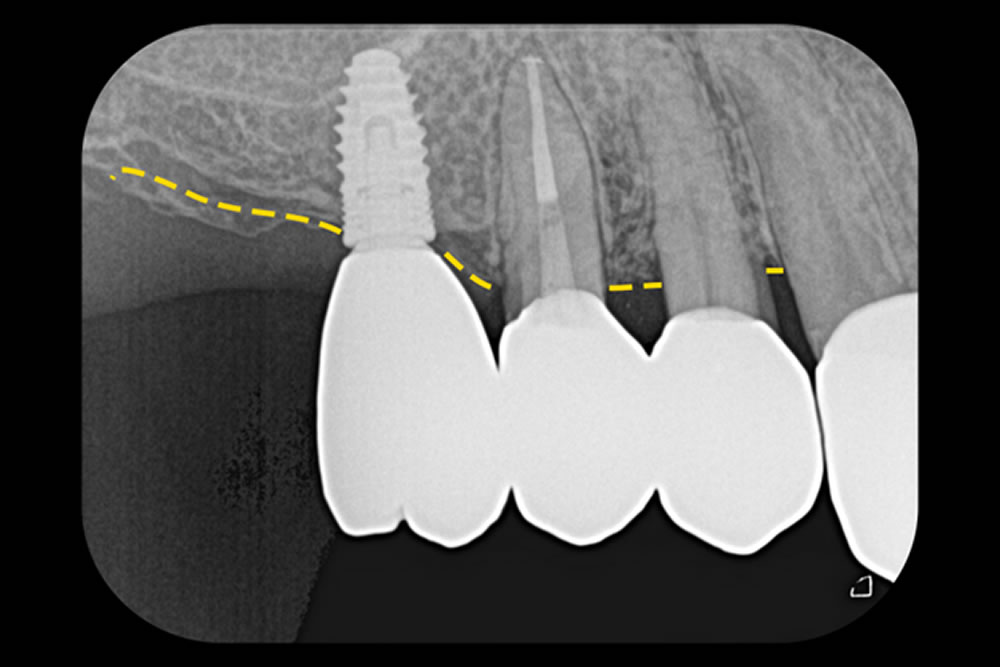

特筆すべき点として、この治療では成長因子や骨補填材などの人工材料を一切使用せず、患者さん自身の血液によってできる「血餅」のみで再生を促しました。血餅には自然な治癒力が備わっており、条件が整えば補助材料がなくても骨の再生が期待できます。術後3年が経過した現在も、歯や骨の状態は安定しており、良好な経過を維持しています。